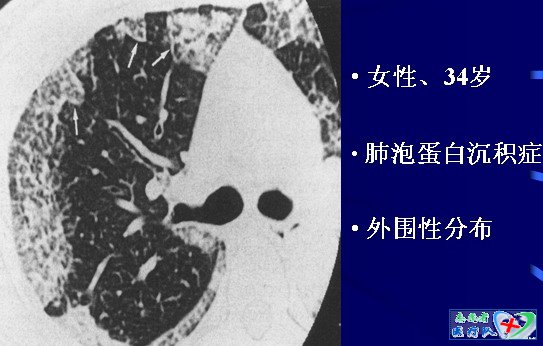

13、“碎石路征”CPA

可见于肺部多种疾病:

8肺泡蛋白沉积症

HRCT 诊断标准:

1.地图样分布的磨玻璃影

2.网格状小叶间隔和小叶内间隔增厚